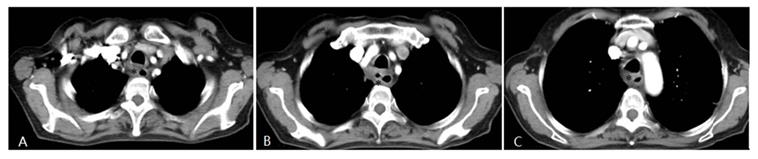

Fig 3

Four weeks after interventional therapy, a chest CT scan shows that the lesion has significantly reduced, tracheal lumen is normal, and the arterial phase enhancement is not apparent (*) (A, B, C).